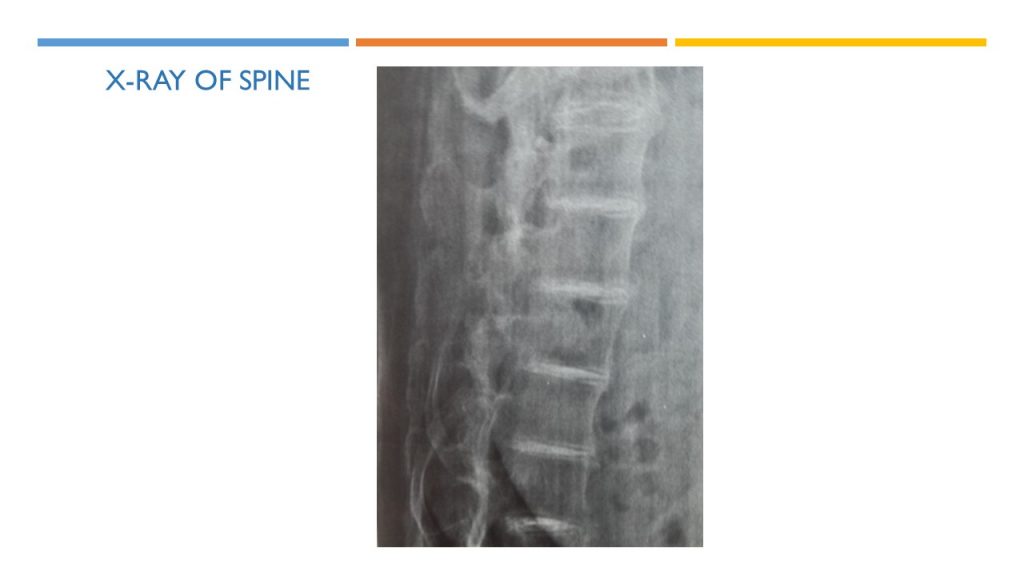

X-ray of spine indicates